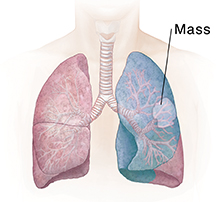

| Lobectomy removes an entire lobe. |

A lung mass or tumor

If a tumor has been found in the lung, a tissue sample (biopsy) can be removed. This piece of abnormal tissue is tested in a lab to find out if the growth is not cancer (benign) or is cancer (malignant). The tissue near the tumor can also be examined to see if the tumor has spread. If the tumor needs to be removed, its size, location, and spread determine how much of the nearby lung also needs to be removed. Removing part or all of a lung is called a lung resection.